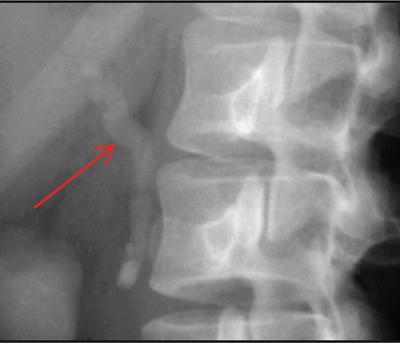

Shrinivas B. Desai, Ritu K. Kashikar, Shreya Shukla Radiological signs are classical and distinctive abnormalities characteristic of a disease. These can be seen on any imaging modality. Resemblance to commonly seen objects and patterns form the basis of radiological signs. The aim is to help the reader associate, understand and memorize these pathologies with the aid of signs. Various signs pertinent to hepatobiliary system are described in the chapter. Described on MRI when liver lesion shows a peripheral rim of high T2 signal intensity with the centre of the lesion appearing isointense to the background of noncirrhotic liver on T2WI mimicking an atoll. It is considered a characteristic sign of an inflammatory hepatic adenoma (image) but is only seen in about one-third of cases Extrinsic smooth impression over medial aspect of duodenum along its posteroinferior aspect, seen in pancreatic head pathologies like carcinoma. This sign is seen in pancreatic adenocarcinoma Presence of a persistently hyperattenuating dot within a lesion on arterial and portal venous CT. This corresponds with peripheral nodular enhancement seen on dynamic MR. Presence of bright dot suggests that the lesion is a hemangioma and helps in ruling out metastasis Ultrasound appearance of multiple cystic spaces or lesions that has been used to describe the appearance of an intraductal papillary mucinous neoplasm of the pancreas. Seen on contrast CT in portal hypertension. The appearance is based on resemblance to Medusa from Greek mythology. Dilated engorged paraumbilical veins radiating across umbilicus to join systemic veins is seen. This sign is seen in Caroli’s disease on contrast CT. Enhancing dots within dilated intrahepatic bile ducts represent portal radicles. Caroli’s disease Irregularly dilated pancreatic duct with multiple strictures and intervening dilatation with associated dilated side ductules resemble multiple lakes supplied by a single territory. Best seen in MRCP images. Chronic pancreatitis It is a finding on MRI and CT and is best seen on MRI T2-weighted and postcontrast T1-weighted sequences. Small necrotic/purulent areas in the pyogenic abscess ‘cluster’ together and then coalesce into a larger necrotic/purulent areas, eventually becoming a larger septated abscess cavity. At the periphery of these clusters: Associated with pyogenic hepatic abscesses and can help differentiate pyogenic abscesses from other types of liver lesions Abrupt termination of gas within the proximal colon at the level of radiological splenic flexure. The inflammatory exudates in pancreatitis extend to the phrenicocolic ligament giving rise to this sign Seen on grey scale ultrasound as a reverberation artifact when small calcific or highly reflective objects are imaged. The colour comet-tail artifact is an ultrasonographic sign seen in a number of situations when colour Doppler scanning is performed. This sign occurs in cases of traumatic right-sided diaphragmatic rupture with resultant partial herniation of liver through the defect. Separation of the herniated liver from its intra-abdominal component is via a small constriction at the level of diaphragm resembling a cottage loaf. Cottage loaf is a particular shape of bread in which larger and smaller roughly spherical balls are squashed together. Traumatic right-sided diaphragmatic rupture with resultant partial herniation of liver Bile eccentrically outlines luminal stone, creating a low attenuation crescent. Best seen on MRCP images. Choledocholithiasis Dilatation of both pancreatic duct and CBD is referred to as the double duct sign. Positive double duct sign suggests the diagnosis of carcinoma of the head of the pancreas and ampullary tumours and is hence considered ominous. Occasionally the sign may be seen in impacted gallstone in the distal duct. This feature is seen in patients with liver abscess on contrast-enhanced CT. A double, inner hyperattenuating and outer hypoattenuating rim is seen surrounding the hypodense abscess. The inner hyperattenuating rim corresponds to the enhancing abscess membrane, while the outer rim corresponds to the edema of the surrounding liver which appears hypodense and may show delayed enhancement. Liver abscess A positive duct penetrating sign is when a mass is penetrated by an unobstructed pancreatic duct; this makes focal pancreatitis the most likely cause rather than pancreatic carcinoma. This sign is best appreciated on MRCP (or ERCP). A radiographic sign that can be useful in differentiating between focal pancreatitis (inflammatory pancreatic mass) from pancreatic carcinoma. The duct-penetrating sign on MRCP is more helpful in differentiating between these two entities than a delayed enhancement pattern on CT or MRI It occurs when there is both limy bile and a gallstone in the common bile duct. The linear vertical radiopaque bile forms the line of the exclamation mark (i.e. !), whilst a more distal calculus forms the ‘dot’ at the end of the exclamation mark. Pathognomonic imaging sign of the rare diagnosis of limy bile on plain abdominal radiography Nonenhancing ruptured lesion with peripheral rim enhancement showing discontinuity from the rest of the liver and protruding from the liver surface is called the enucleation sign. Ruptured HCC Enlargement of the pericholecystic space. One of the signs of liver cirrhosis Can be seen on technetium 99m sulphur colloid scans of the liver and spleen, as well as CT studies. It occurs as a focal area of increased radiopharmaceutical uptake in the medial segment of the left hepatic lobe (segment IV) occurring as a result of SVC obstruction and portosystemic venous shunting between the superior vena cava and the left portal vein via the internal thoracic and paraumbilical veins. The equivalent of this sign may also be seen on contrast-enhanced CT scans as a hypervascular region. Budd–Chiari syndrome causes the hot spot sign in the caudate lobe

2) Antral pad sign